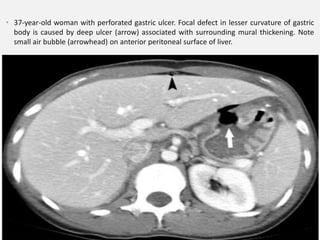

• 37-year-old woman with perforated gastric ulcer. Focal defect in lesser curvature of gastric

body is caused by deep ulcer (arrow) associated with surrounding mural thickening. Note

small air bubble (arrowhead) on anterior peritoneal surface of liver.